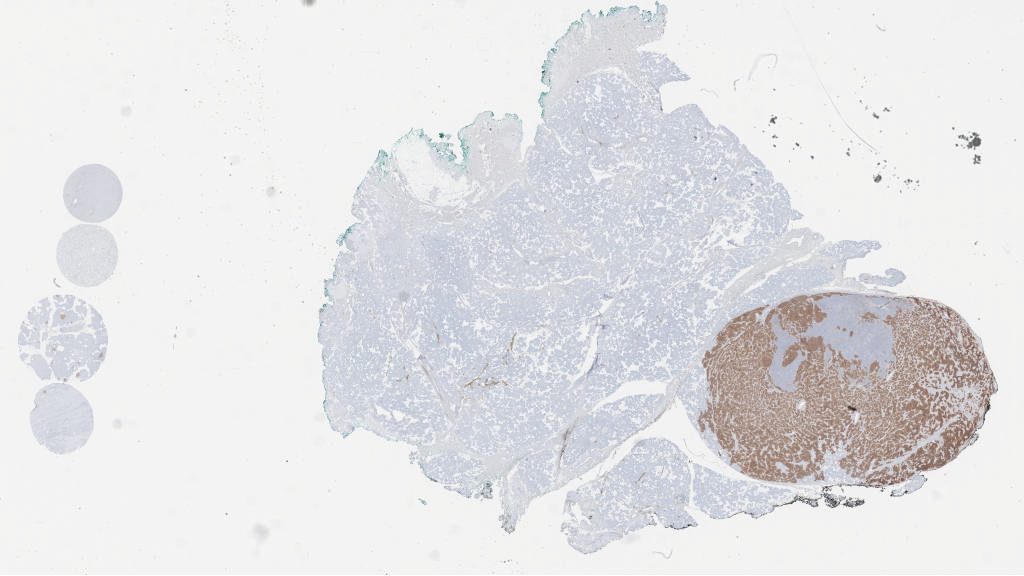

599898.svs

147408

82840

40X